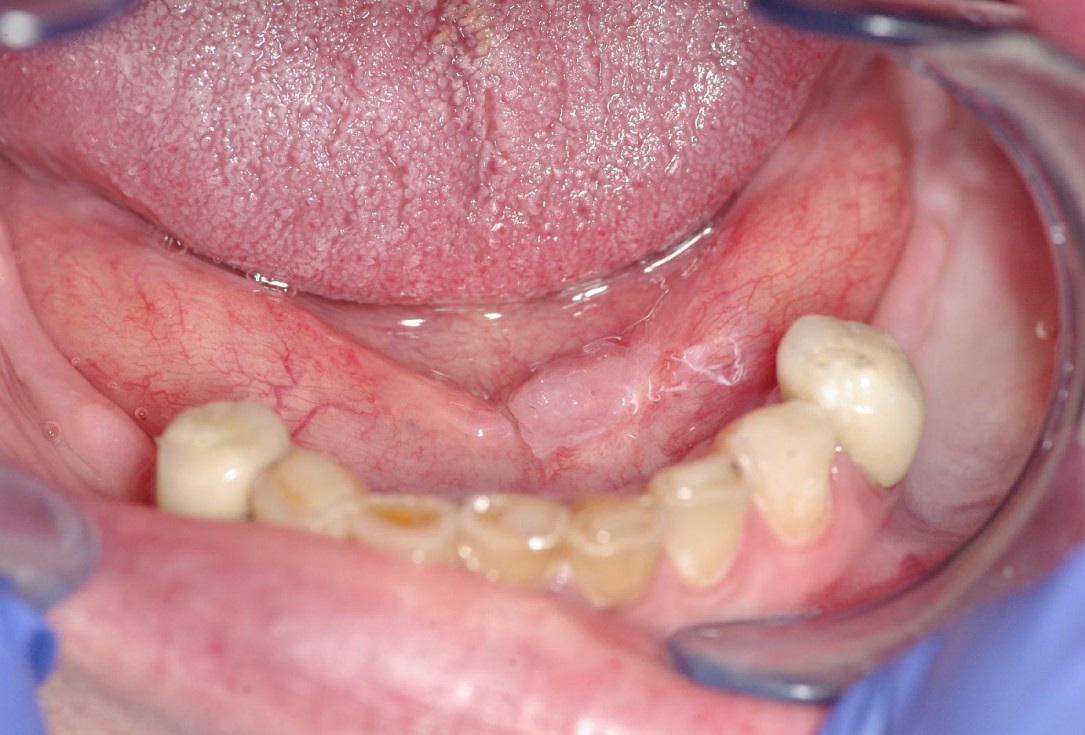

1/7 - Initial clinical situationmucoderm® for soft tissue augmentation after resective surgery - Dr. Dr. P. Kämmerer